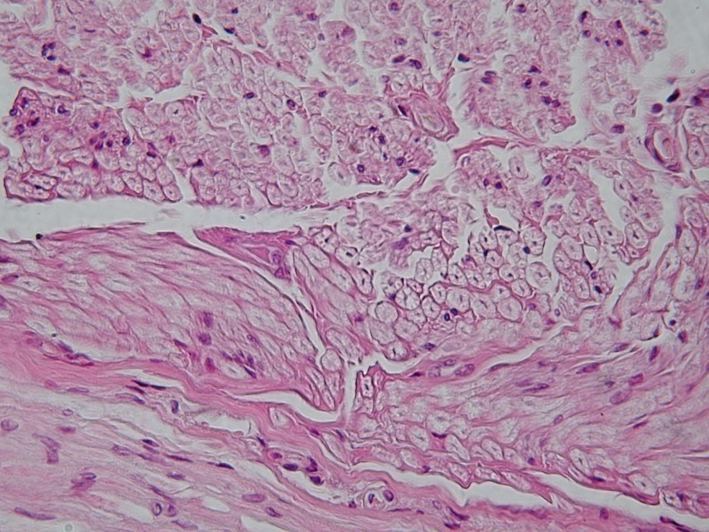

2. connective

• Connects body parts (connects, supports and binds) Cell secrete EXTRACELLULAR MATRIX -Fibers and “adhesion proteins” -able to form a soft padding around the other tissues -able to bear weight -able to withstand stretching

1. bone

1. cartilage

1. hyaline

1. fibrocartilage

1. elastic

2. dense

2. loose